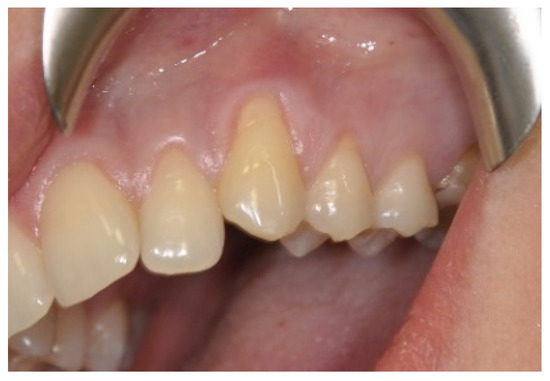

3. Results

3.1. Clinical Measurements for CAL and GRD

3.2. Clinical Measurements for GRW, PD and AG